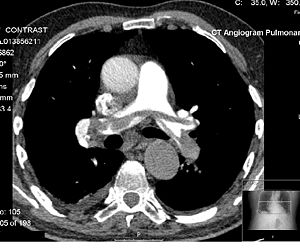

Chest

CT can be used for detecting both acute and chronic changes in the lung parenchyma, that is, the internals of the lungs. It is particularly relevant here because normal two dimensional x-rays do not show such defects. A variety of different techniques are used depending on the suspected abnormality. For evaluation of chronic interstitial processes (emphysema, fibrosis, and so forth), thin sections with high spatial frequency reconstructions are used—often scans are performed both in inspiration and expiration. This special technique is called High resolution CT (HRCT). HRCT is normally done with thin section with skipped areas between the thin sections. Therefore it produces a sampling of the lung and not continuous images. Continuous images are provided in a standard CT of the chest.

For detection of airspace disease (such as pneumonia) or cancer, relatively thick sections and general purpose image reconstruction techniques may be adequate. IV contrast may also be used as it clarifies the anatomy and boundaries of the great vessels and improves assessment of the mediastinum and hilar regions for lymphadenopathy; this is particularly important for accurate assessment of cancer.

CT angiography of the chest is also becoming the primary method for detecting pulmonary embolism (PE) and aortic dissection, and requires accurately timed rapid injections of contrast (Bolus Tracking) and high-speed helical scanners. CT is the standard method of evaluating abnormalities seen on chest X-ray and of following findings of uncertain acute significance.

Pulmonary angiogram

CT pulmonary angiogram (CTPA) is a medical diagnostic test used to diagnose pulmonary embolism (PE). It employs computed tomography to obtain an image of the pulmonary arteries.

It is a preferred choice of imaging in the diagnosis of PE due to its minimally invasive nature for the patient, whose only requirement for the scan is a cannula (usually a 20G).

MDCT (multi detector CT) scanners give the optimum resolution and image quality for this test. Images are usually taken on a 0.625 mm slice thickness, although 2 mm is sufficient. Fifty to 100 mls of contrast is given to the patient at a rate of 4 ml/s. The tracker/locator is placed at the level of the Pulmonary Arteries, which sit roughly at the level of the carina. Images are acquired with the maximum intensity of radio-opaque contrast in the Pulmonary Arteries. This is done using bolus tracking.

CT machines are now so sophisticated that the test can be done with a patient visit of 5 minutes with an approximate scan time of only 5 seconds or less.

A normal CTPA scan will show the contrast filling the pulmonary vessels, looking bright white. Ideally the aorta should be empty of contrast, to reduce any partial volume artifact which may result in a false positive. Any mass filling defects, such as an embolus, will appear dark in place of the contrast, filling / blocking the space where blood should be flowing into the lungs.